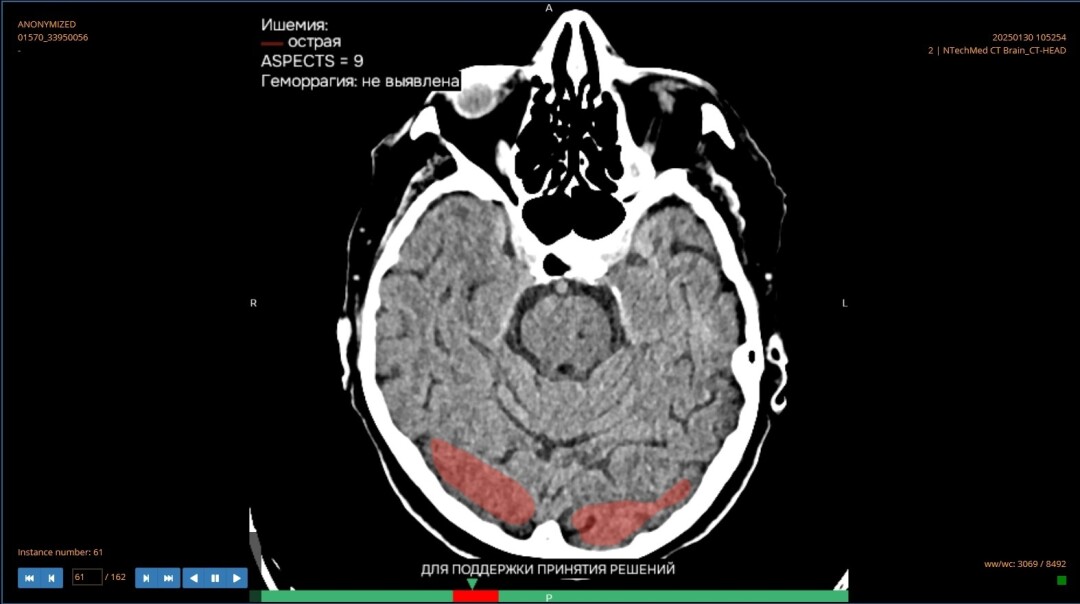

Снимок опубликовал Айрат Рахматуллин

Сегодня, 30 января, министр здравоохранения Башкортостана Айрат Рахматуллин сообщил о том, что искусственный интеллект помог проанализировать 1,7 тысячи медицинских изображений в Башкортостане – всего за два месяца работы с платформой «МосМедИИ».